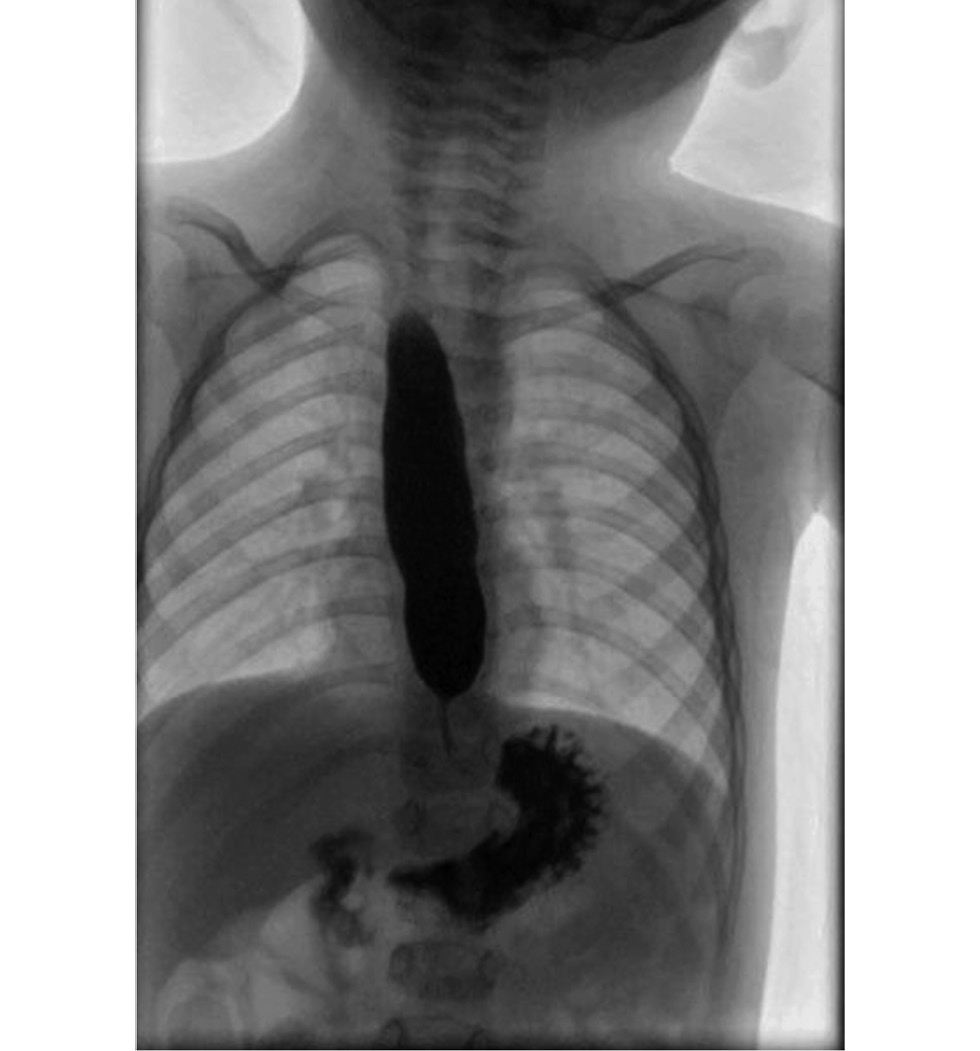

На основании эзофагографии, эзофагогастродуоденоскопии и манометрии пищевода был поставлен диагноз «ахалазия кардии» (рис. 1). Решено выполнить хирургическое вмешательство с использованием роботизированной технологии.

Рис. 1. Эзофагография пациента с ахалазией пищевода.

Fig. 1. Esophagography of the patient with esophageal achalasia.